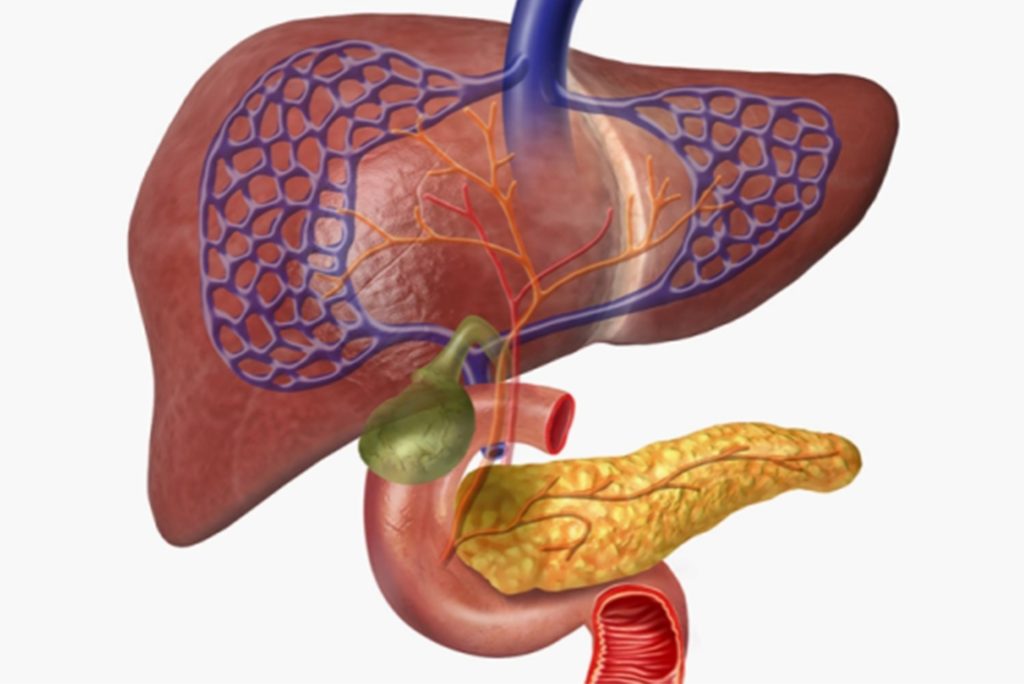

جدير بالذكر أن البنكرياس يقوم بإنتاج إنزيمات تساعد على الهضم، ويطلق هرمونات مثل الإنسولين لتنظيم مستويات السكر بالدم.